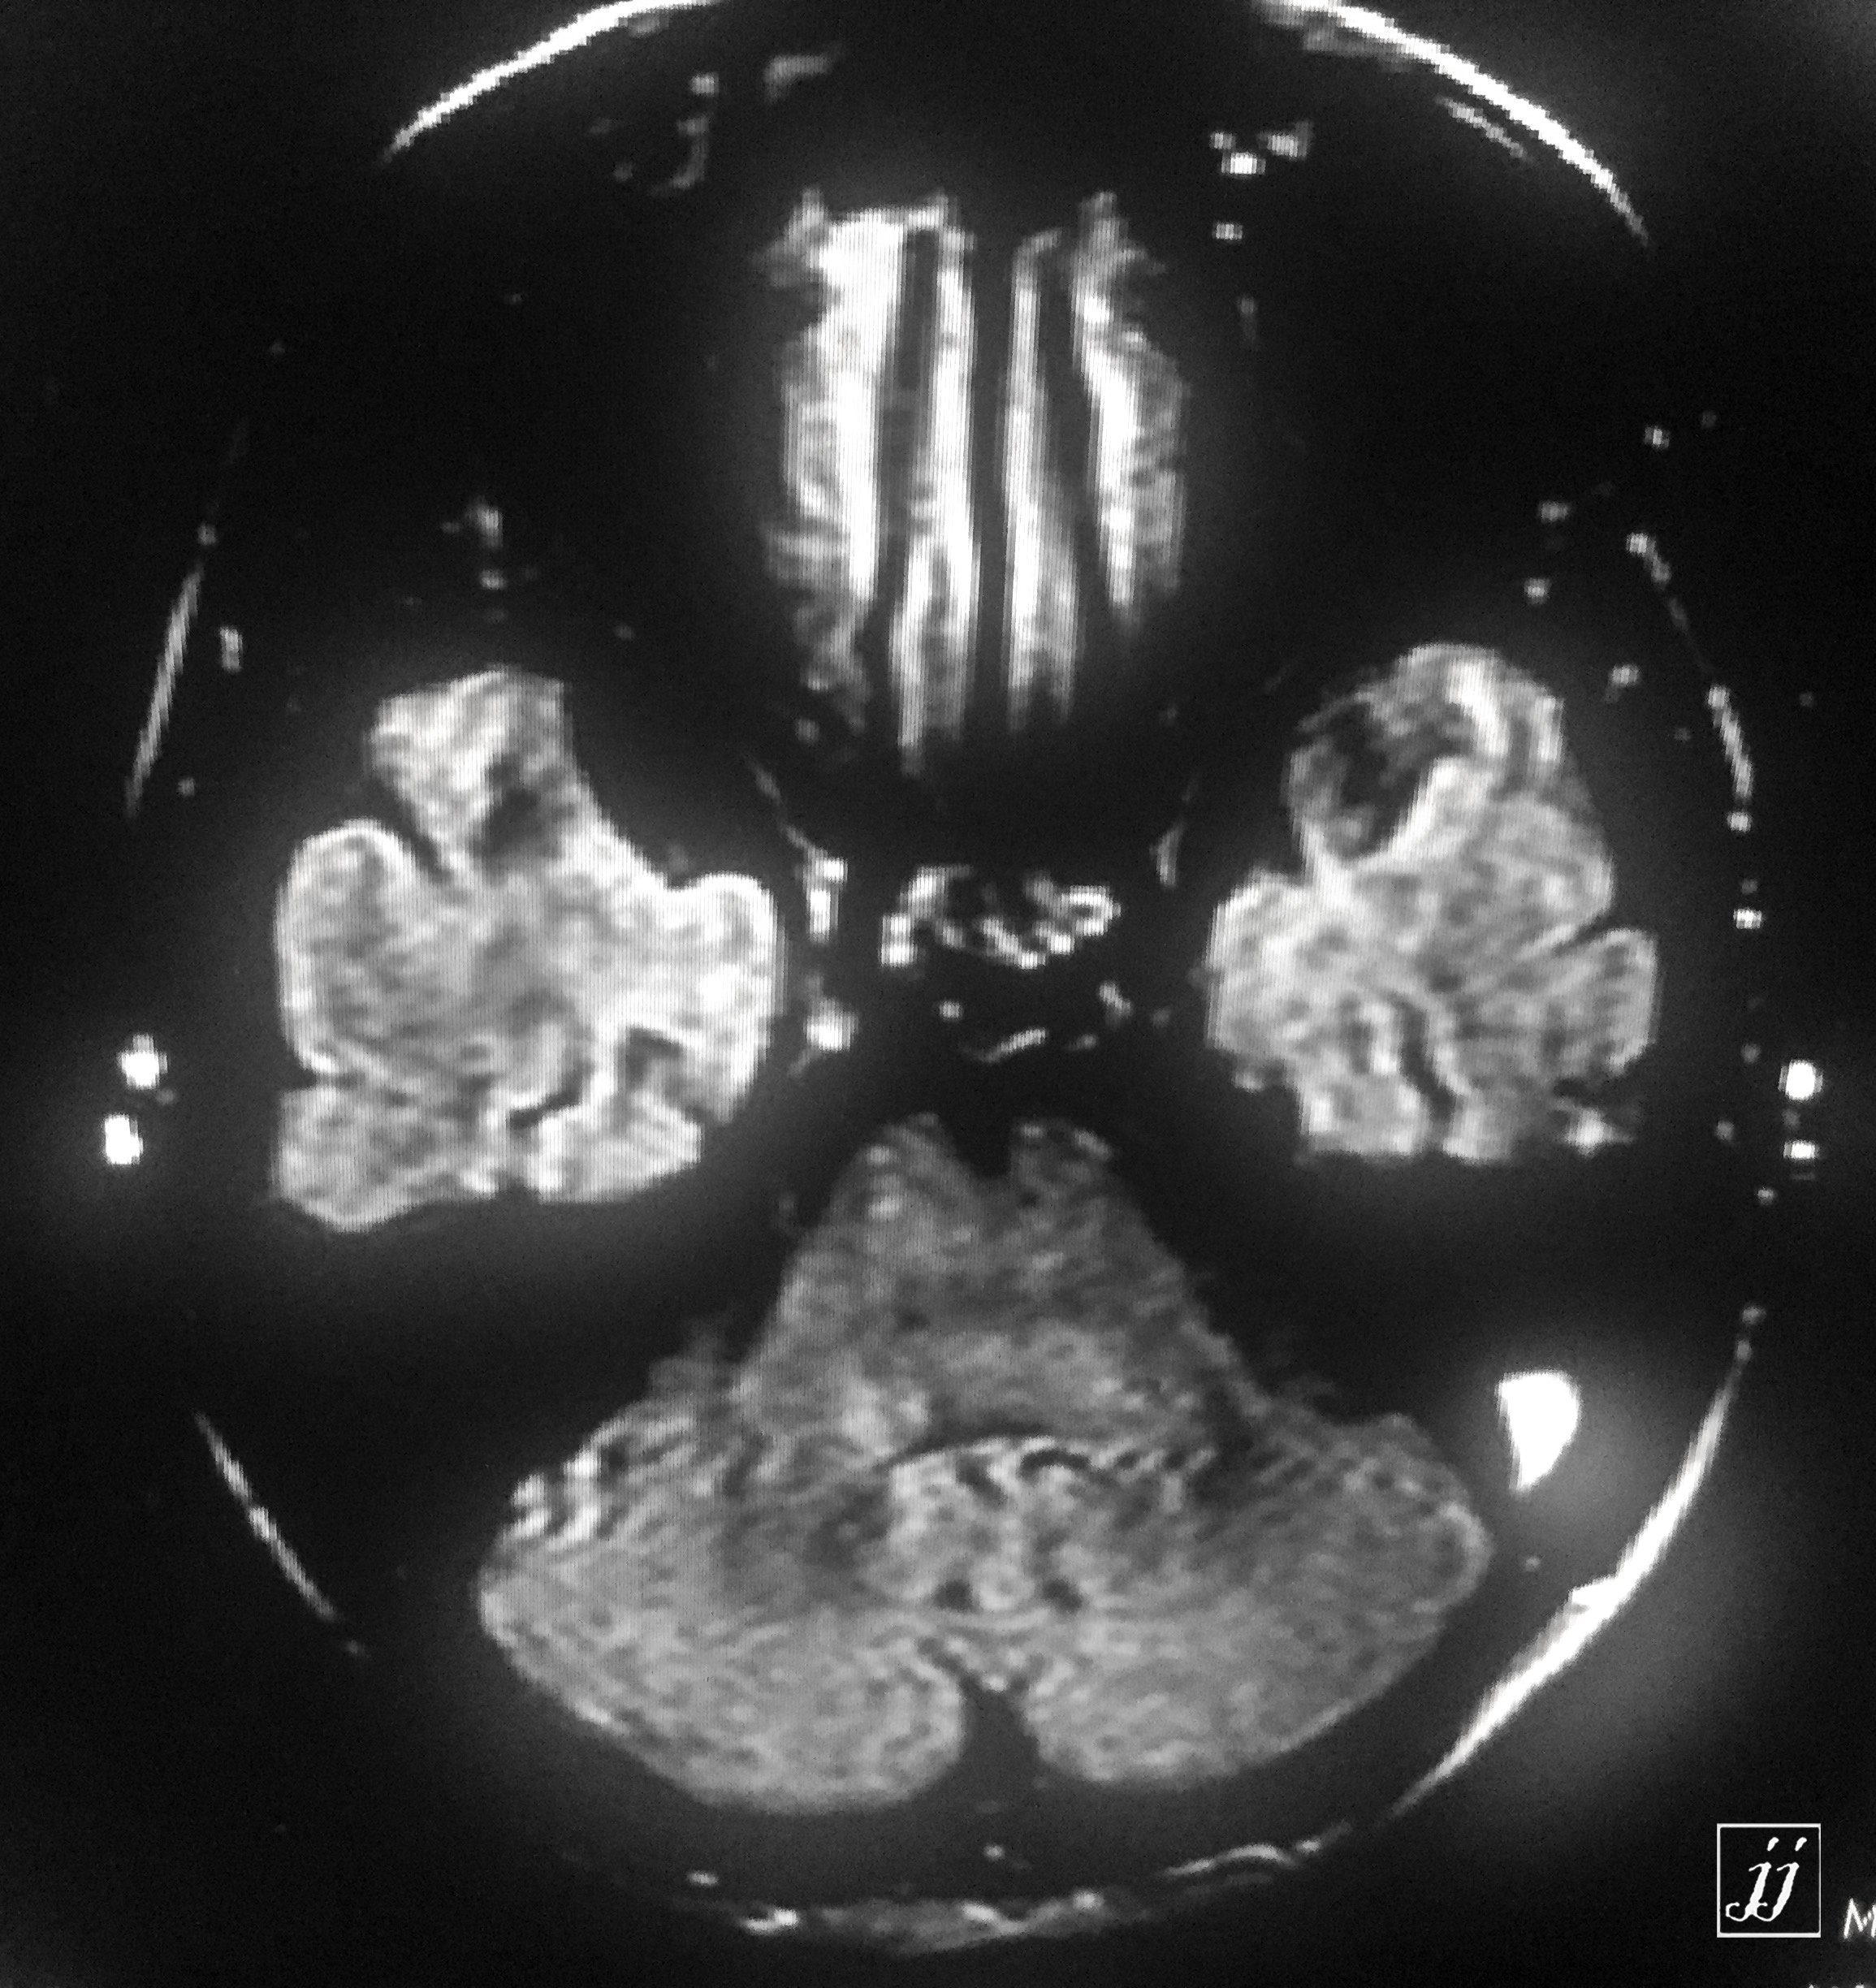

Brain- left mastoid abscess (4)